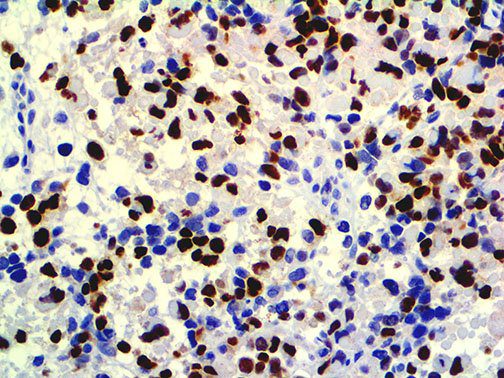

It is the ICU physician who is most likely to witness one of the deadliest manifestations of the abnormal immunological response, the cytokine storm syndrome (CSS). This response is also referred to by some as the cytokine release syndrome (CRS). CSS is characterized by continuous activation and expansion of macrophage and lymphocyte populations, which secrete large amounts of cytokines, causing the cytokine storm. This massive cytokine release is akin to hemophagocytic lymphohistiocytosis (HLH) disease, a syndrome characterized by initial unchecked and persistent activation of cytotoxic T lymphocytes and NK cells.

Clinical and laboratory manifestations of HLH include fever, enlarged liver and/or spleen, neurologic dysfunction, coagulopathy, liver dysfunction, cytopenias (i.e., low levels of erythrocytes, leukocytes, and/or platelets), hypertriglyceridemia, hyperferritinemia, hemophagocytosis, and eventually diminished NK cell activity as the immune system becomes progressively paralyzed. HLH can be familial (primary HLH) or secondary to another disease process (sHLH), such as rheumatic disease, in which it is referred to as macrophage activation syndrome (MAS, characterized by elevated ferritin).